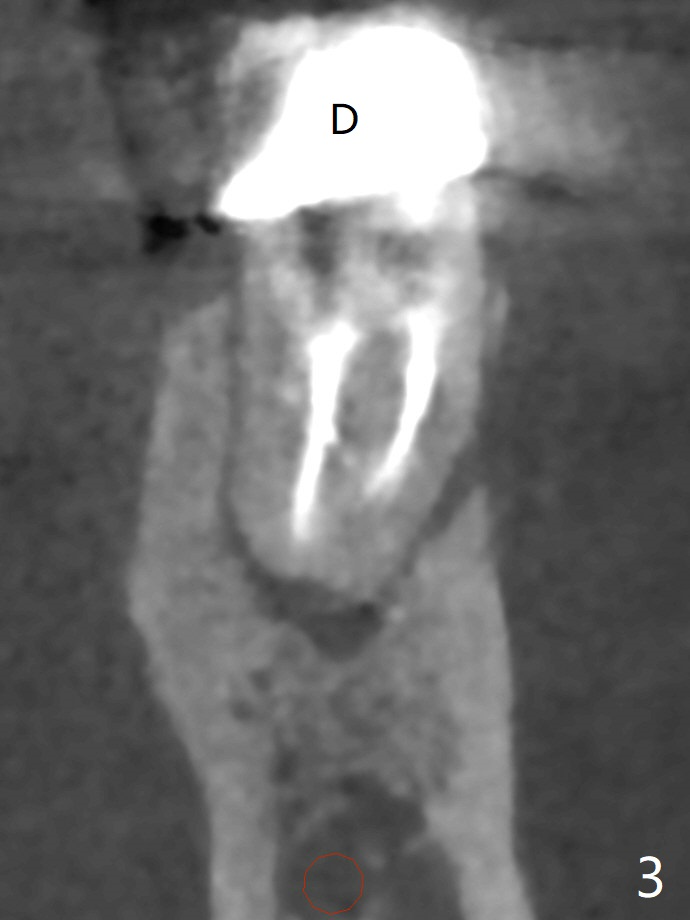

The tooth #19 of a 61-year-old man develops pain 9 years post complicated RCT (Fig.1). Periradicular radiolucency is more around the mesial root (Fig.2) than the distal one (Fig.3). Section the crown to check whether the distal margin is restorable. Remove the mesial root to determine whether the distal one is salvageable or not. If not, place a 5x15 mm bone-level implant with guide. To reduce the chance of screw loosening, consider placing a tissue-level implant (Fig.4,5). Preserve the buccal crestal bone (Fig.6 *) during extraction and debridement, which keeps the socket open for bone graft and healing. Draw blood for PRF PRN for membrane and sticky bone.